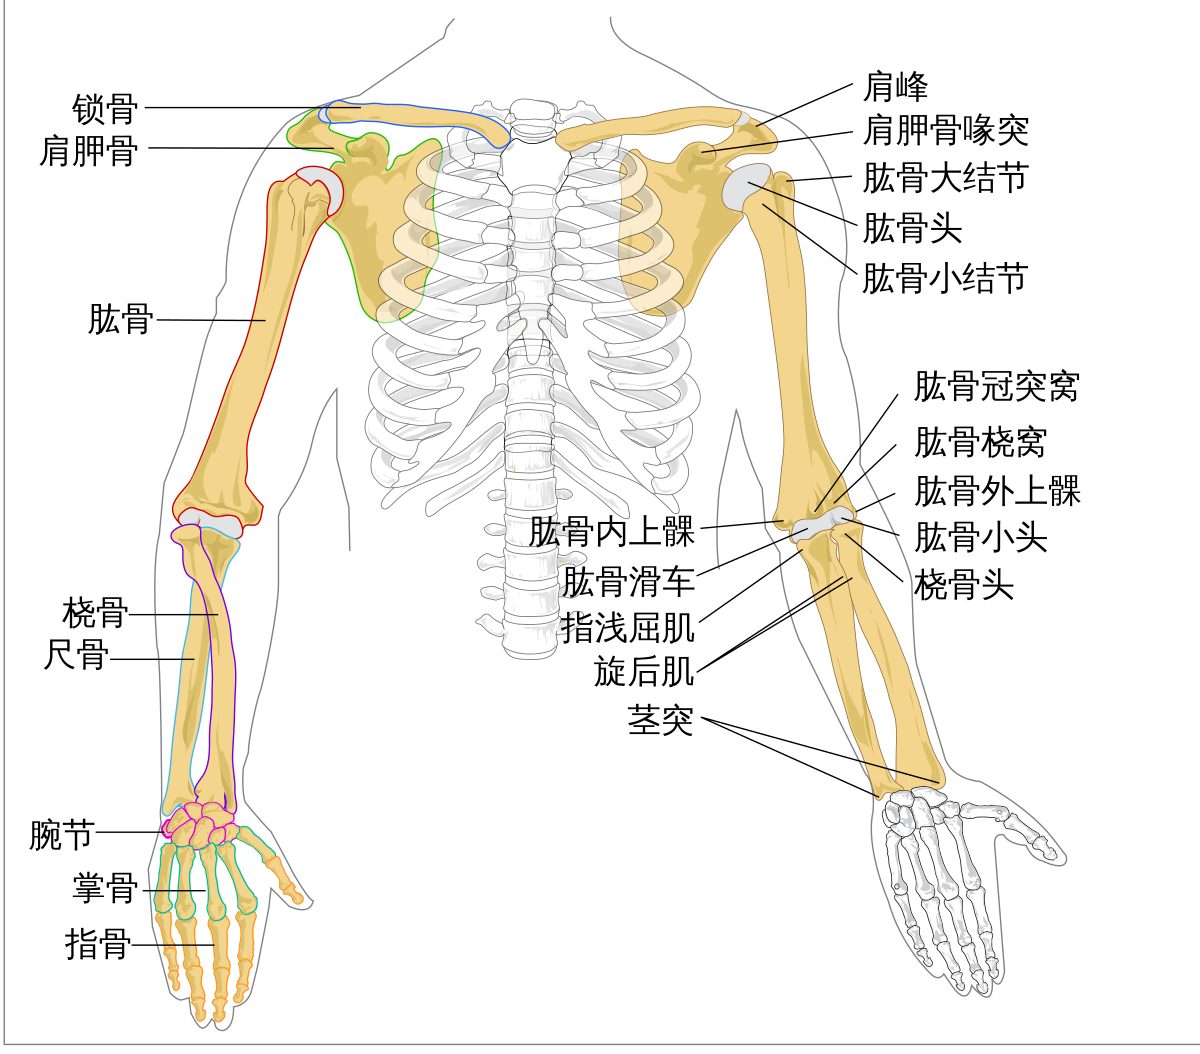

臂 维基百科 自由的百科全书

肱骨 Humerus 小小整理網站smallcollation

肱骨 Humerus 小小整理網站smallcollation

肱骨 维基百科 自由的百科全书

肱骨 肱骨 位於上臂 又叫上臂骨 上端有半球形的肱骨頭與肩胛骨的關節盂組 百科知識中文網

肱骨 Wikiwand